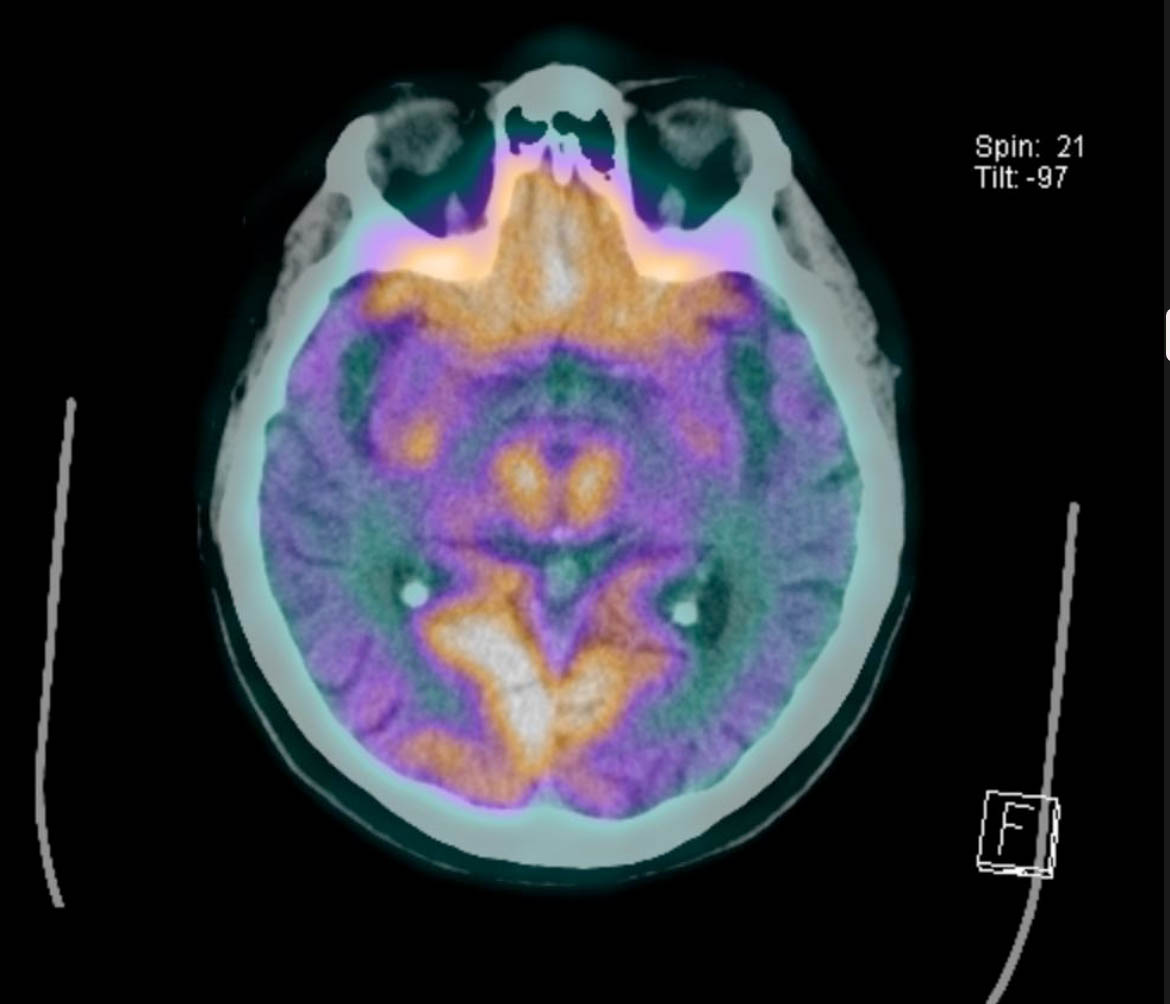

Imagen de PET-CT en enfermo con Alzheimer en que las zonas de color naranja son normales, pero extensas zonas de su corteza cerebral no se aprecian del mismo color (zonas de daño).

Siendo popularmente conocida como demencia senil o "arterioesclerosis cerebral". El Dr. Milton Quiroz, neurorradiólogo de centro de diagnóstico San Lorenzo destaca “Gracias a los avances en tecnología de imagen médica con los que contamos a nivel mundial, y ahora también en nuestro centro de diagnóstico y para toda la zona centro sur. Hoy podemos retrasar su progresión, e incluso, adelantarnos al diagnóstico en varios años antes de que empiece el deterioro, permitiendo a médicos especialistas que atiendan a pacientes con sospechas y su familia, planificar mejor el futuro. Por nuestra parte como centro de diagnóstico, nos propusimos en el 2017 contar con un PET-CT para este tipo de estudios, y hoy en 2019 ya estamos ad portas de adquirir un nuevo resonador magnético de 3 teslas, que gracias a su alto campo magnético y calidad en imagen (Mayor resolución en imagen), podremos disponer de mejor tecnología en estudios al cerebro, sin variación en precios para que pueda ser accesible para la mayoría de la población”.